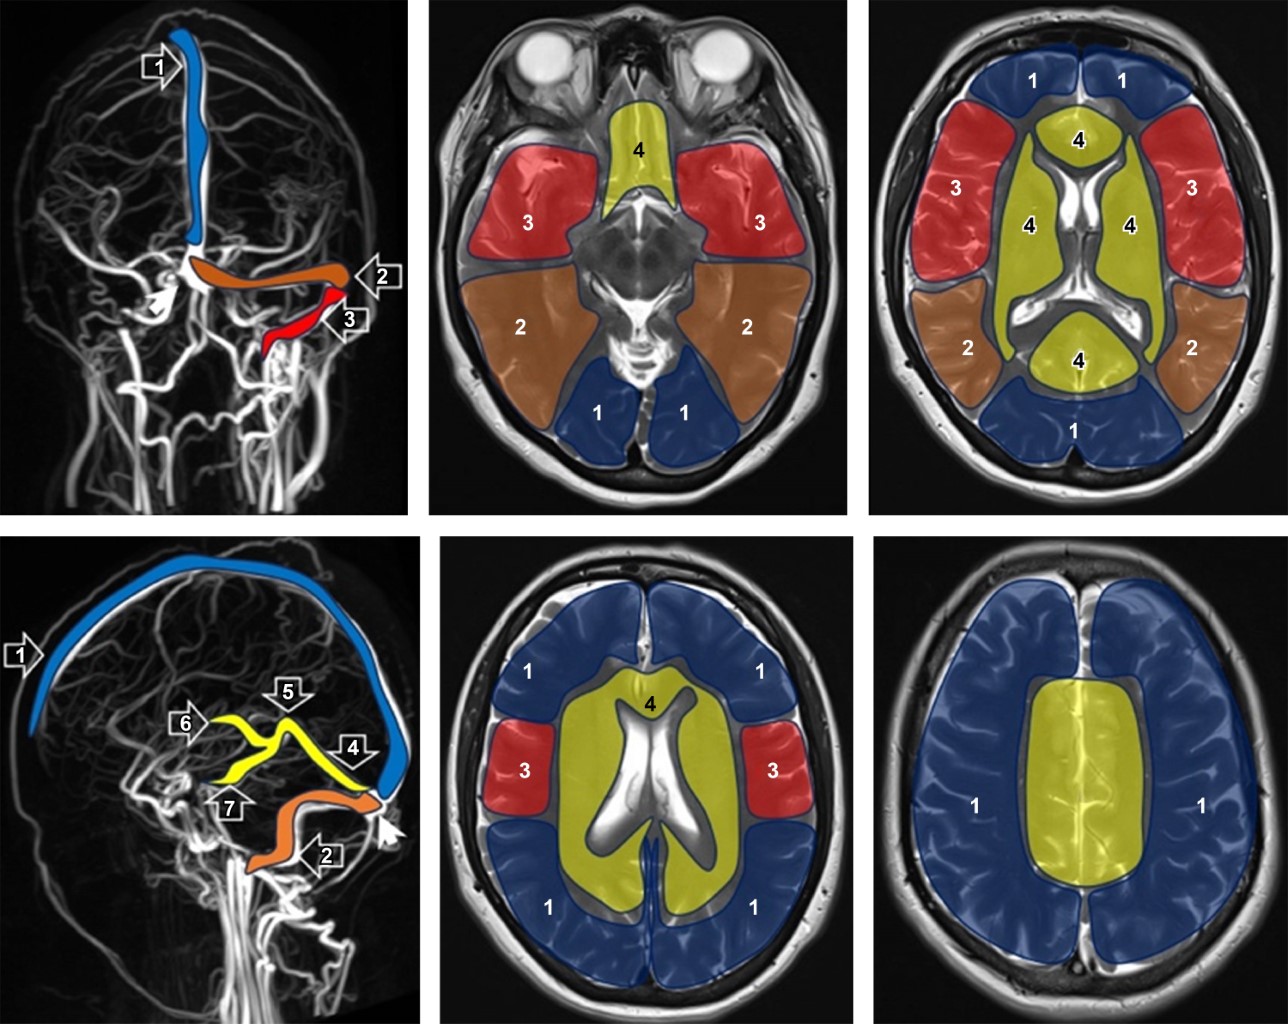

El diagnóstico se realiza mediante resonancia magnética (RM) en combinación con venografía-RM (Figura 1), una técnica no invasiva que permite identificar el trombo venoso y los cambios en el parénquima cerebral.3-5 El uso de heparina y anticoagulantes orales se basa en la reversión del proceso trombótico y prevención de complicaciones, mejorando notablemente el pronóstico de la TVC en los últimos 30 años.2,3,5

Figura 1